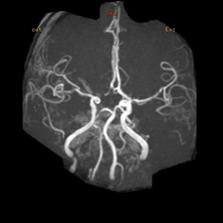

脑动脉开窗畸形通常在尸检或者影像学检查时被发现。CTA和MRA不仅能够无创地显示开窗畸形的位置、形态和毗邻结构,还能显示伴发的其它病变,是脑动脉开窗畸形2种最佳的诊断方法。当脑动脉开窗畸形难以跟动脉夹层进行鉴别时,可以考虑行脑血管造影检查,进行三维重建便可进一步帮助鉴别。